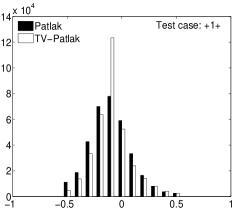

In the images shown in the figures we illustrate the calculated uptake rates of the FDG. Images for the CMRGlc can be obtained by directly scaling . In figure 1 we compare the result of using Patlak and TV-Patlak for estimating the uptake rates with respect to no noise, noise in the input function, Poisson noise in the sinogram, and finally with respect to the case in which the irreversibility assumption is violated but without noise in the sinogram or input data. In each case the histogram of the relative errors is given on the left, the Patlak image in the middle and the TV-Patlak on the right. The different scales in the histograms are due to the total number of results illustrated. When there is no noise (triples and ) the histogram illustrates results over all voxels but only one simulation, while for the noisy simulations the results are for all voxels over all realizations of the noise. The TV-Patlak images are more homogeneous in all cases and the relative errors are smaller. The figures clearly show the improvements of employing the TV-Patlak method as compared to using Patlak independently for each voxel. This is confirmed in figure 2 in which images with noise in the sinogram, positive and different noise levels in the input function are shown.

Quantitative measurements, confirming the illustrations, are presented in table 3. There we also present the results for conventional Patlak’s method with post-smoothing by two standard filters:

Consistent with the observation in [21, 16], we find that violation of the Patlak assumption, , introduces about bias; when but for . The rows (std) and “# 10% (#15%)” provide complementary supporting information, indicating that the TV is minimized by TV-Patlak; as compared to Patlak, Patlak-GF and Patlak-MF the number of voxels with larger error is reduced. In particular, we emphasize that TV-Patlak provides a better noise removal mechanism than popular post-filtering approaches.

In figures 3 and 4 we illustrate the uptake rates and relative error in the uptake rates, respectively, calculated by Patlak, TV-Patlak, Patlak-GF and Patlak-MF for one simulated data case , i.e. , noise in the input function and Poisson noise in the sinograms. The uptake rate image generated by Patlak-MF is visually smoother than that by TV-Patlak, but the equivalent histograms show that the relative error is higher for Patlak-MF than for TV-Patlak; the Patlak-MF image is over-smoothed.